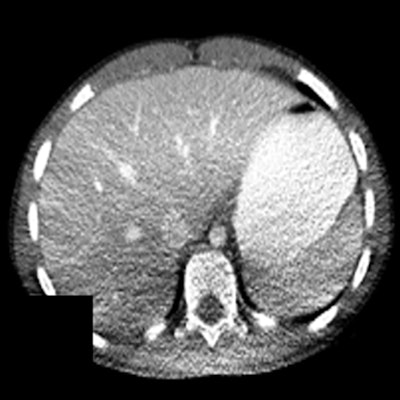

Figure 3. Anterior (top) and lateral (bottom) positions of the x-ray tube when the patient is (a) in the center of the gantry (b) shifted anteriorly (c) shifted posteriorly with respect to the beam output. Reproduced from Barreto et al.5This can cause nonuniform noise in the image following reconstruction. Moreover, possible shading artifacts may occur due to beam hardening from changes in the mean beam energy that can lead to artifactual changes in organ density (Fig. 4).7

Figure 4. Shading artifacts as a result of beam hardening can be seen on the CT scan in the posterior region of the patient, causing an artifactual change in liver density. Reproduced from Szczykutowicz et al.7

Figure 4. Shading artifacts as a result of beam hardening can be seen on the CT scan in the posterior region of the patient, causing an artifactual change in liver density. Reproduced from Szczykutowicz et al.7Vertical and lateral shifts: quantified